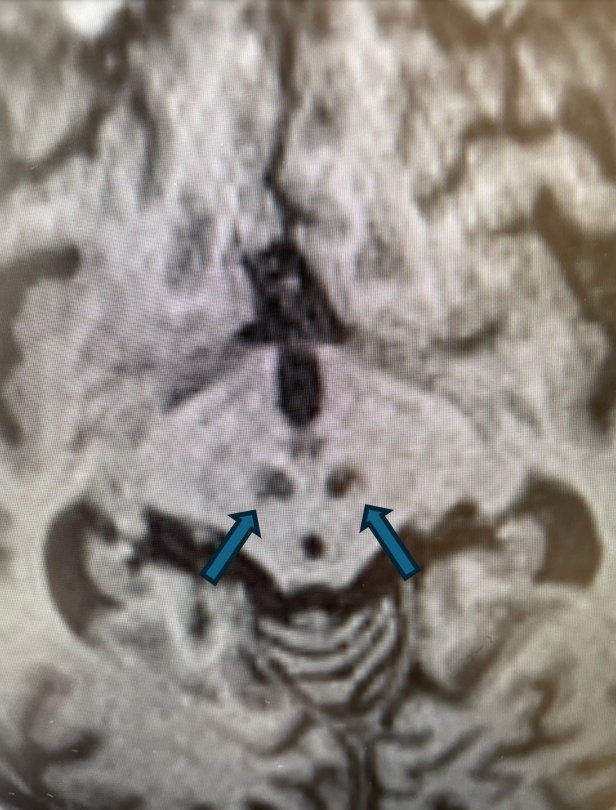

Rycina 4. Cechy akumulacji jonów żelaza w obrębie jąder zębatych móżdżku (T1).

rycinka